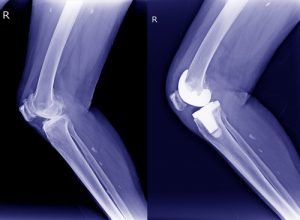

- Замена коленного сустава – сложная операция с различными вариантами проведения. Возможна установка одномыщелкового протеза, протеза с подвижной системой, связной сустав и другие варианты.